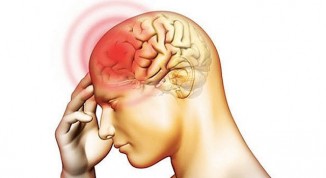

რა აუცილებელი ზომები უნდა მივიღოთ ინსულტის დროს ექიმის მოსვლამდე.

ინსულტი- ( აპოპლექსური შეტევა ) - ტვინში სისხლის მიმოქცევის მკვეთრი დარღვევა, ტვინის ქსოვილების დაზიანება და მისი ფუნქციის მოშლაა. დაავდება სწრაფად..